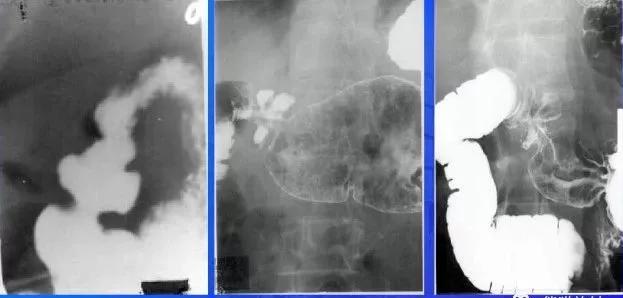

十二指肠反“3”字征(细箭头)及“垫征”(粗箭头)

胰头癌:胃肠造影示十二指肠扩大,内测缘出现压迹,呈“反3”征

左图上箭头示十二指肠降段内侧小憩室,憩室颈部狭窄,内见气液平面

右图右箭头示意憩室周围肠黏膜皱襞增粗,排空延长,提示憩室炎症

钡餐造影示:十二指肠第二、三段两个向腔外突出的憩室